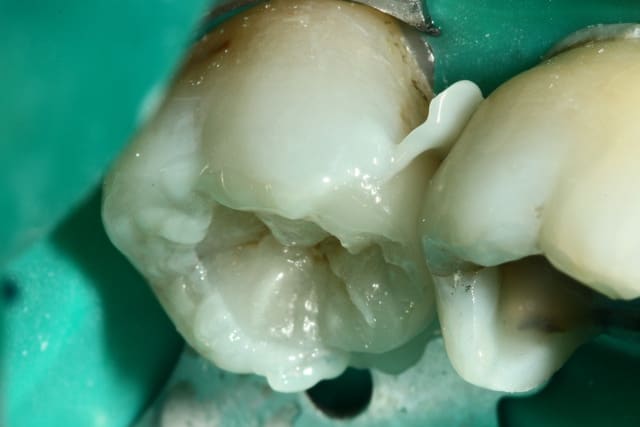

Photo 1. Moi: "Voilà pourquoi il vous faut un onlay."

Photo 3. Le patient: "Ah quand même! Ben on va faire les autres alors!"